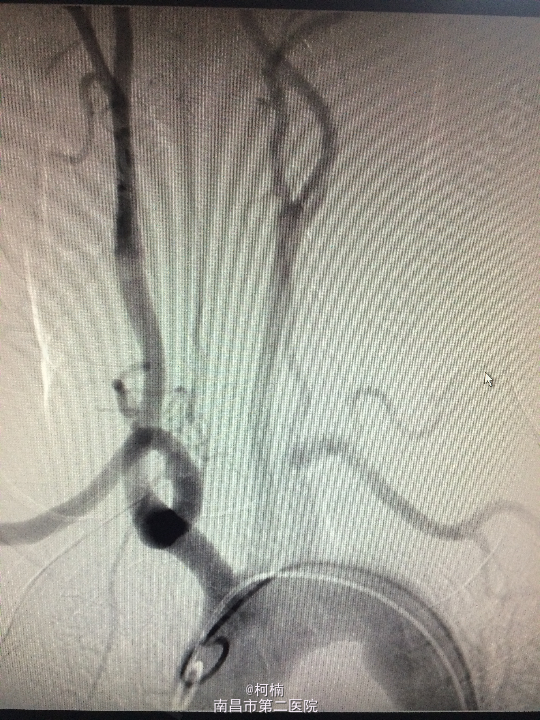

诊断:右侧小脑脑膜瘤 处理:先行介入栓塞肿瘤供血动脉,再行开颅手术治疗,术后予组织病理检查,提示:脑膜瘤